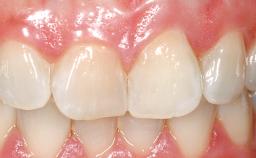

Late Placement of an Implant in a Maxillary Left Central Incisor Site

A 36-year-old female patient was referred for the replacement of the upper left central incisor (tooth 21), which had fractured. Although the tooth had been asymptomatic for many years, the crown began to loosen, at which time she presented to her dentist for an assessment. Teeth 21 and 22 had both been endodontically treated many years previously. She was a healthy individual and a non-smoker.

On examination, the patient had a low lip line and only displayed the coronal half of the anterior teeth when smiling.

Abutment Type Customized

Prosthesis Type FDP